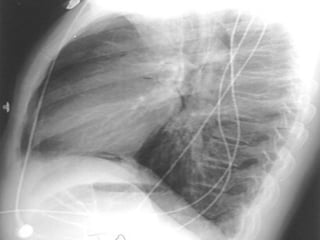

Necrotizing Pneumonia / Lung Abscess / Aspiration

Superior segment RLL dense pneumonia

Progression / Cavity